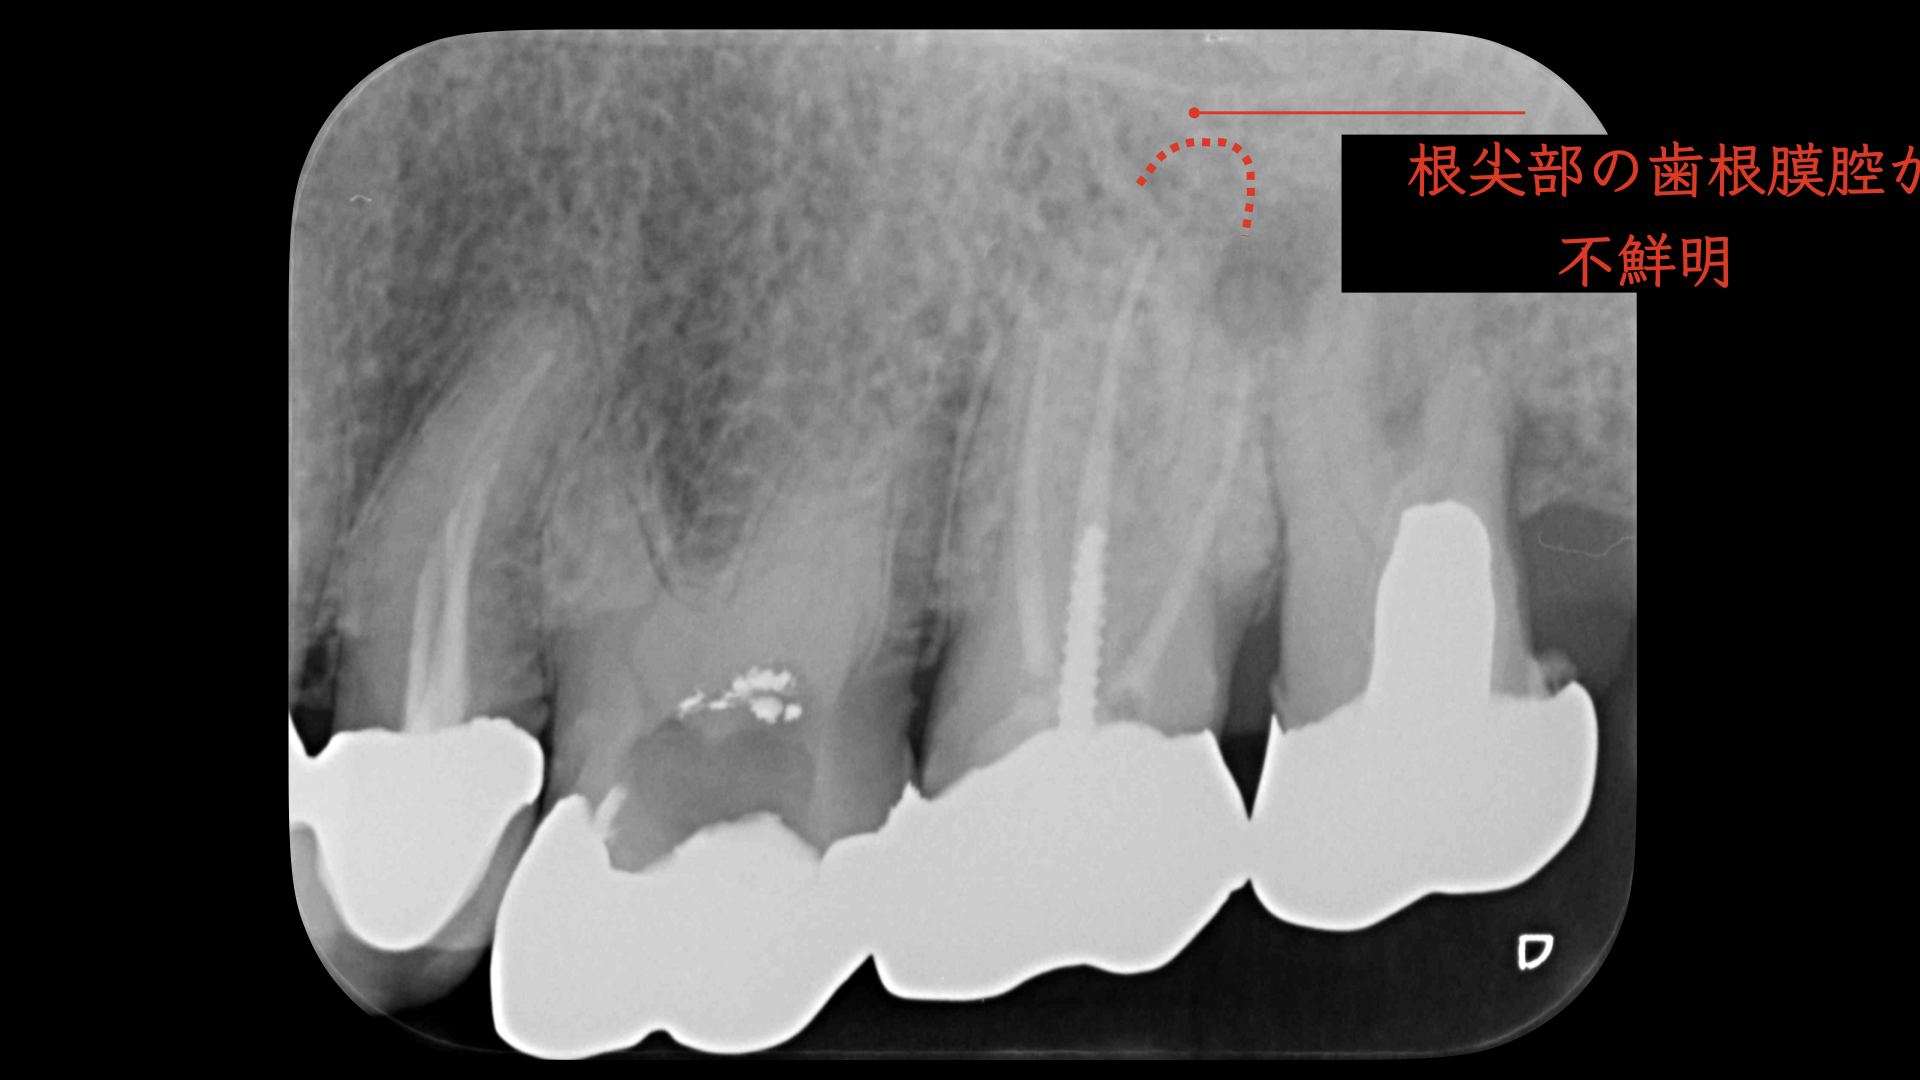

右の画像のCT上で根尖部にかなり大きな透過像があります。